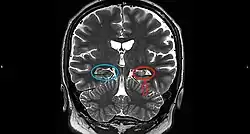

On an MRI T2-weighted or T2–fluid‐attenuated inversion recovery (FLAIR) scan, hippocampal sclerosis appears as an increased signal, smaller sized (atrophic) hippocampus with a less well-defined internal structure.[2] Increased signal means that hippocampal sclerosis will appear brighter on the MRI image. Less well-defined internal structure means the expected sharp boundaries between hippocampal gray and white matter structures are absent.[2] The total volume of the hippocampus is also reduced.[2] The reduced volume arises from neuronal cell loss, and increased signal arises from gliosis.[2]